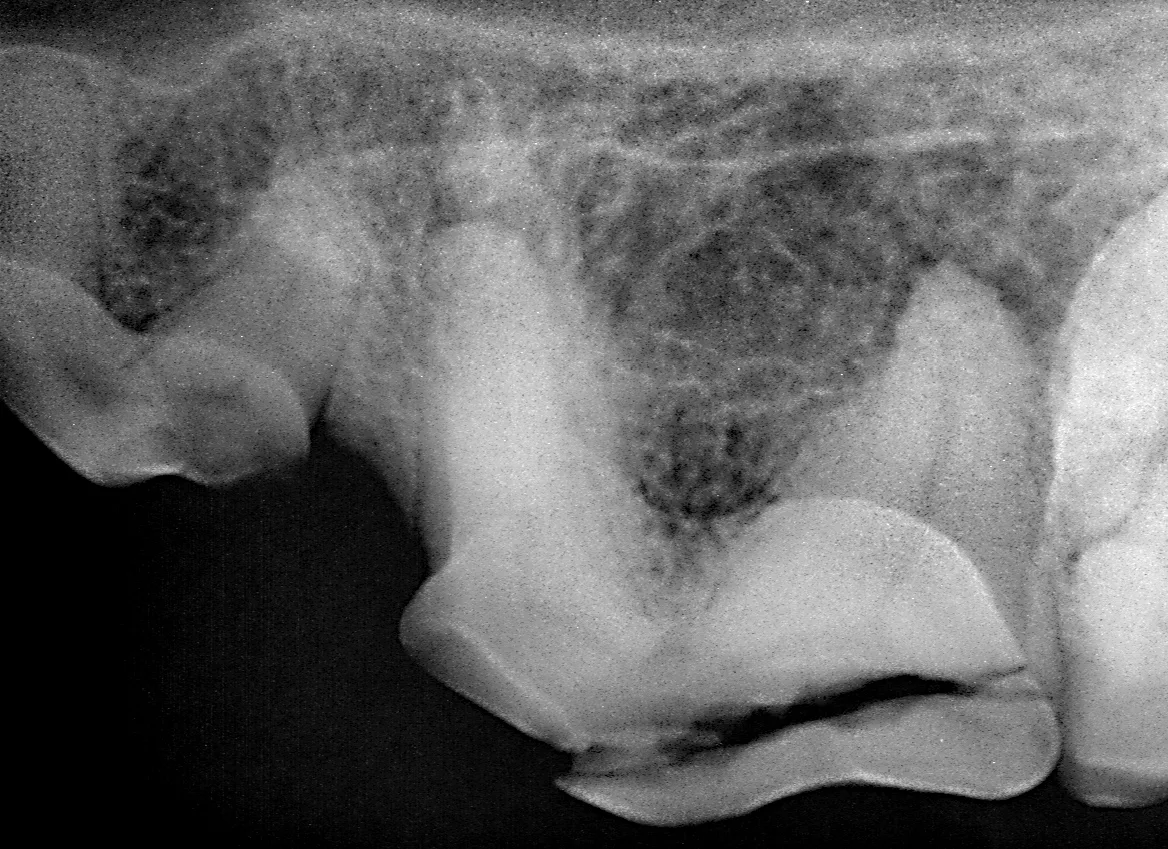

The patient is anesthetized, dental radiographs taken, tooth assessed, and multimodal pain management, including dental nerve block, instituted.

Preoperative radiograph of the maxillary left 4th premolar